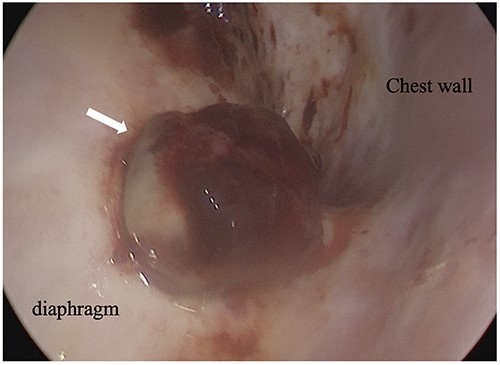

An 81-year-old man who underwent surgical resection for lung cancer 2 years previously was referred for the examination of a right diaphragmatic mass that was pointed out during follow-up. Computed tomography (CT) revealed pleural effusion and two contrast-enhanced nodules (17 × 10 and 10 × 10 mm) in the right diaphragm (Fig. 1A); however, he had no symptoms. Positron emission tomography (PET)/CT was performed, but no FDG accumulation was found (Fig. 1B). Although hemangioma was suspected based on the preoperative imaging, we were unable to exclude the recurrence of lung cancer. Therefore, the patient was admitted for the examination of the right diaphragmatic nodules by VATS. A 4-cm thoracotomy wound was created at the 8th intercostal mid-axillary line, and a 5.5-mm port was created at the 6th intercostal anterior axillary line. Observation of the thoracic cavity revealed reddish brown pleural effusion and two large and small pedunculated tumors on the diaphragm (Fig. 2). The smaller nodule spontaneously fell off during the process of cleaning the thoracic cavity and was submitted for a rapid intraoperative diagnosis. As hemangiomas were diagnosed during the operation, the roots of the smaller nodule and the larger nodule that fell off were treated using an ultrasonic coagulation and incision device while partially leaving the abdominal layer of the diaphragm. Partial excision was performed (Fig. 3). The nodules were 1.7 × 1.7 and 1.5 × 1.5 cm with a brown surface (Fig. 4). Histopathologically, the nodules were mostly blood clots, and a collection of thin-walled blood vessels with red blood cells was observed (Fig. 5A). An immunohistochemical analysis revealed that the vascular endothelial cells were positive for CD31 and CD34 (Fig. 5B). Thus, the nodules were diagnosed as diaphragmatic hemangioma. No hemangiomatous lesions were noted in the normal connective tissue in the additional resected tissue specimens (Fig. 6). The postoperative course was normal, and the patient is being followed up in an outpatient setting. It has been 16 months since the operation, but no recurrence has been observed at this time.

Intraoperative thoracoscopic image, and the diaphragm layer was peeled off with the active blade of the ultrasonic coagulation and incision device.

In partial resection in the clinical setting, the use of an electric scalpel is difficult because electrical stimulation stimulates the movement of the diaphragm. Therefore, in this case, the operation was performed using the active blade of the ultrasonic coagulation and incision device, and the root excision operation was completed.